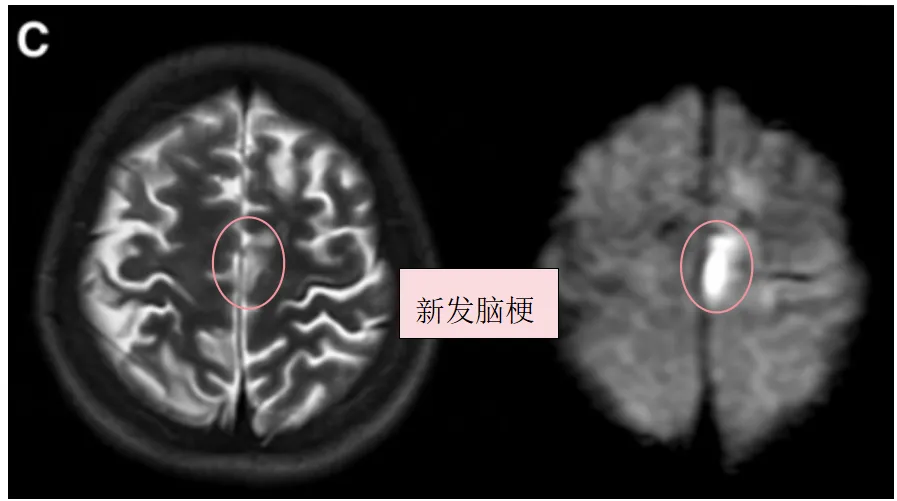

1个月后,幸子因构音障碍和右腿无力入院,并在左额叶出现新的脑梗死(图1C,D)。随后出现甲状腺风暴。(fT4 3.91 ng/ml,fT3 10.09 pg/ml)

图1C:术前T2、DWI序列显示左额叶新发展的脑梗死